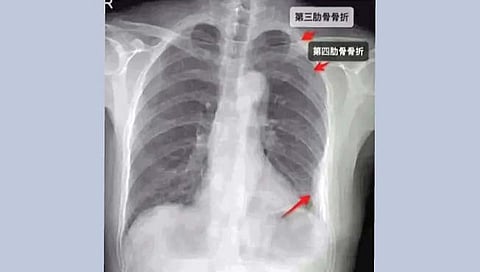

पाच दिवसांनंतरही वेदना कमी न झाल्याने ती हॉस्पिटलमध्ये गेली. तिथे एक्स-रे काढल्यावर तिच्या तीन बरगड्यांना दुखापत झाल्याचे दिसून आले. तिने आपल्या सहकार्याविरुद्ध कोर्टात धाव घेतली व न्यायालयाने तिला 10 हजार युआन म्हणजेच सुमारे 1.16 लाख रुपयांची मदत देण्याचा आदेश तिच्या सहकार्याला दिला.